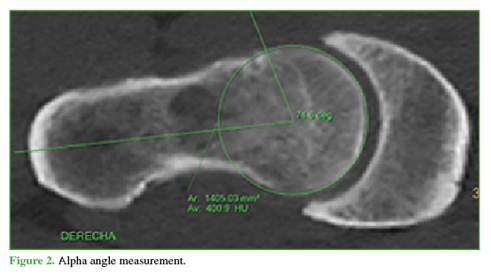

Morphological abnormality: Radiographs were reviewed to classify deformities as Pincer, Cam, or Mixed. For acetabular overcoverage (Pincer), the lateral center-edge angle (Wiberg angle, normal 25°-40°) and the acetabular index (normal 0°-10°) were measured, as well as the acetabular wall crossover sign. For femoral deformity, the alpha angle was measured on the Dunn 45° projection, with <55° (Warwick) considered normal (Figure 2). All measurements were performed by imaging specialists not involved in the study.